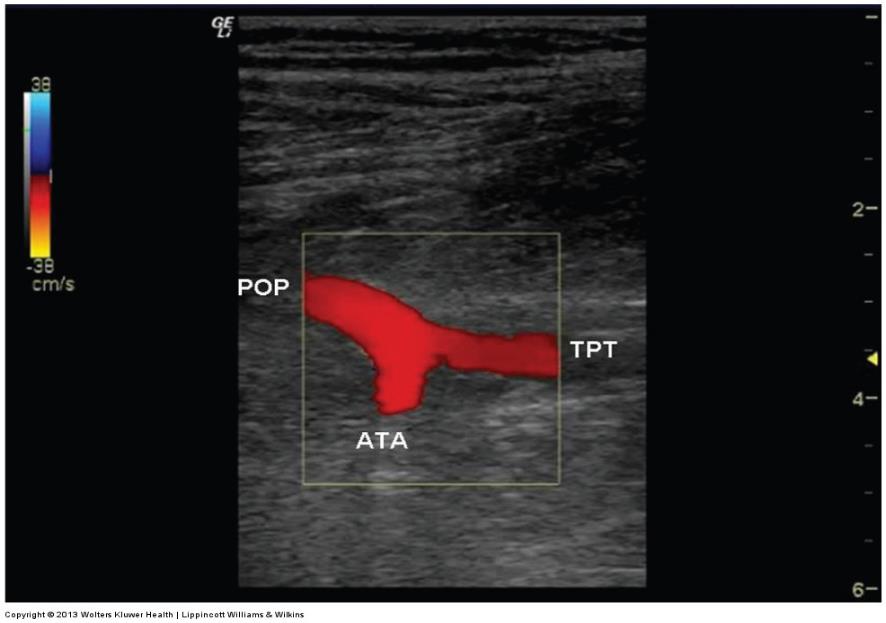

ultrasound image of the origin of the anterior tibial artery (ATA) off the popliteal artery w/ the tibioperoneal trunk